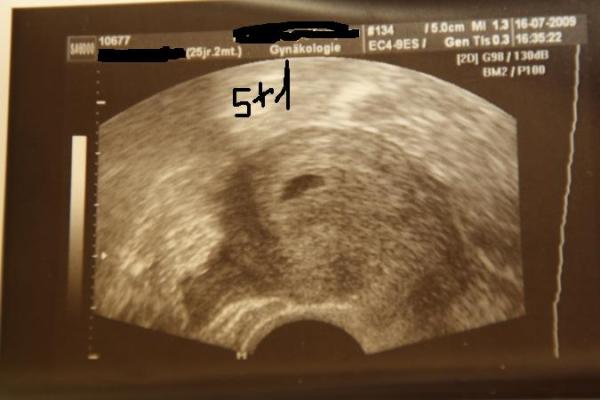

ah ok danke dann passt das e dazu also bei mir hat man in der 6 ssw nur eine aufgebaute schleimhaut gesehen erst in der 8 ssw ... war dann ne fruchthöhle da mit ner bohne .. oder sogar noch kleiner :D anbei ein bild ;)

Bild zu